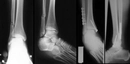

Ayak ezilmesi geçiren biri olarak, iyileşme sürecim oldukça zorlu geçti. Şişlik ve ağrı ile başa çıkmak zorundaydım. Genel olarak ayak ezilmesi kaç günde geçer diye merak ediyorum, çünkü bu durumun süresi kişiden kişiye değişiyor gibi görünüyor.

Ayak Ezilmesinin İyileşme Süreci

Ayak ezilmesi, gerçekten zorlu bir deneyim olabilir. İyileşme süresi birçok faktöre bağlı olarak değişiklik göstermektedir. Genellikle, hafif ezilmelerde birkaç gün içerisinde iyileşme sağlanabilirken, daha ciddi durumlarda bu süre bir hafta veya daha uzun sürebilir.

Yaş, genel sağlık durumu, yaralanmanın ciddiyeti ve tedavi yöntemleri gibi etkenler iyileşme sürecini etkileyebilir. Ayrıca, dinlenme, buz uygulama ve gerekirse fizik tedavi gibi yöntemler de iyileşme sürecini hızlandırabilir.